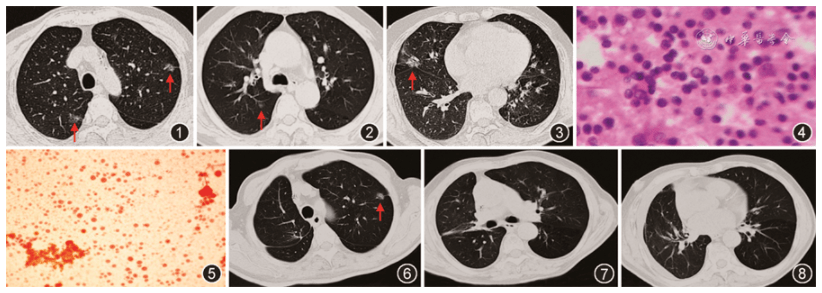

病例报告以反复淡黄色澄清胸腔积液为特征的肺癌术后迟发性乳糜胸一例

肺癌患者出现乳糜胸和乳糜心包1例 患者,男,年龄70岁,既往每年吸烟80